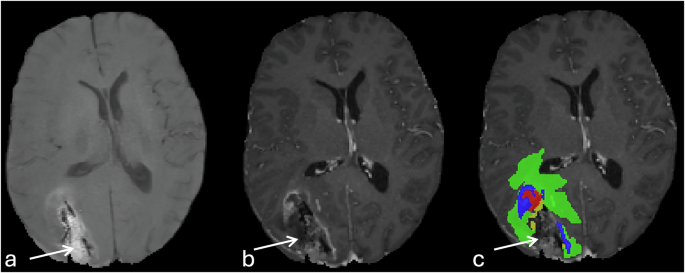

Erroneous inclusion of T1 hyperintensity and misclassification as enhancing tumor component (Fig. 5).

Fig. 5 Misclassification of the T1 shortening of the resection cavity rim as enhancing tumor label. Peripheral T1 hyperintensity of the anteromedial and posteromedial margins of the resection cavity (a), without change in T1 following IV gadolinium-based contrast administration (b). Note wrong assignment of the enhancing tumor label (blue, c).

T1 hyperintense signals within the resection cavity were incorrectly and misclassified as non-enhancing hemorrhagic tumor component instead of blood products within the resection cavity (Fig. 6).

Fig. 6 An example of misclassification of T1 hyperintensity within the center of the resection cavity. T1 hyperintense material within the resection cavity with fluid level, and foci of pneumocephalus without corresponding enhancement (arrows, a & b). The segmentation overlay image shows the wrong assignment of the T1 hyperintensity as enhancing tumor (blue), and non-enhancing tumor core (red).